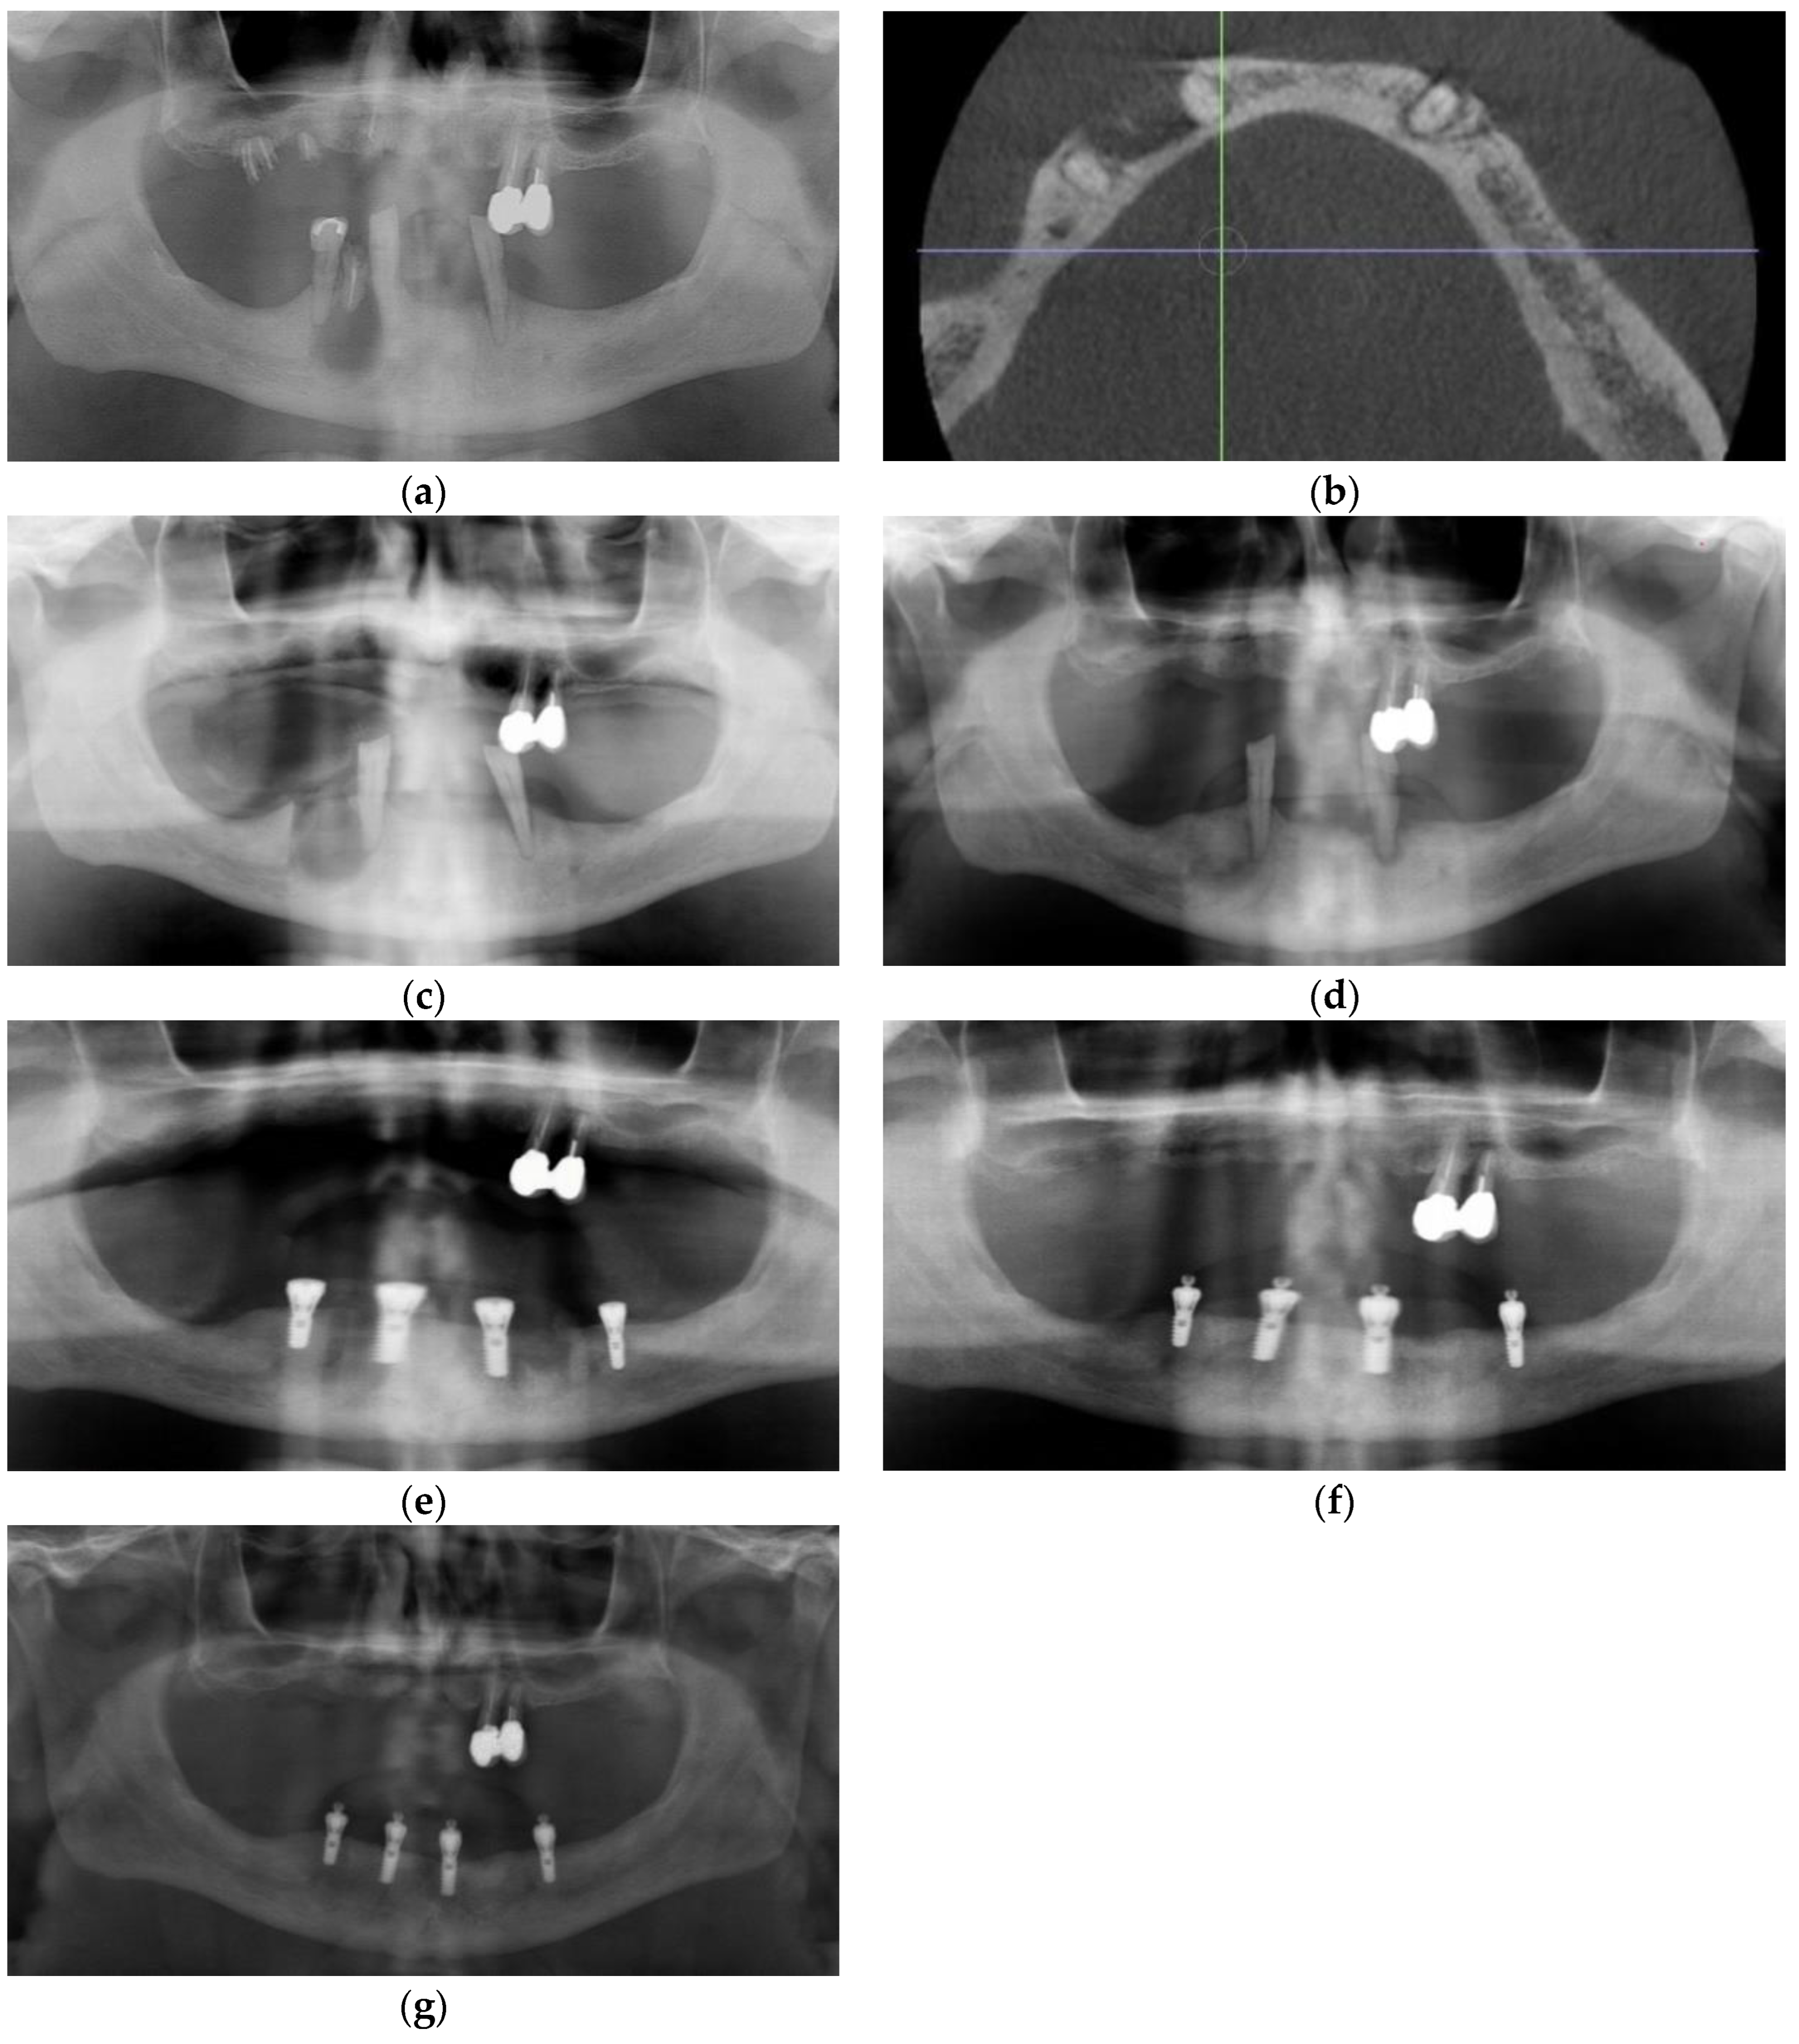

3.2. Case 2